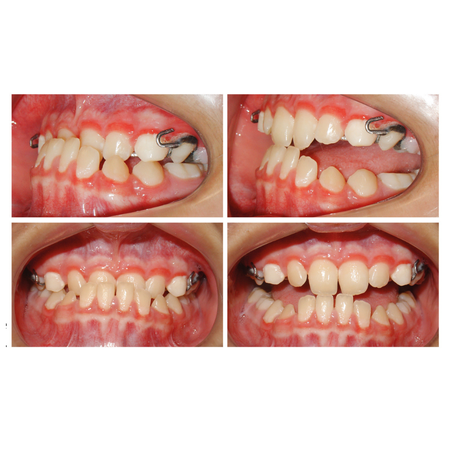

Fechamento de espaços com mini-implantes em paciente Classe III esquelética com agenesia dentária múltipla: relato de caso

INTRODUÇÃO: O gerenciamento dos espaços das agenesias dentárias é frequentemente relatado como um desafio adicional para o tratamento ortodôntico e, quando associado à má oclusão esquelética, torna o tratamento mais complexo. OBJETIVO: Neste relato de caso, objetivou-se apresentar um tratamento ortopédico seguido de tratamento ortodôntico compensatório de um paciente Classe III esquelética severa com agenesia dentária múltipla. RELATO DE CASO: Paciente do sexo masculino, com...

Space closure with mini-implants in a skeletal Class lll patient with multiple tooth agenesis: case report

INTRODUCTION: Space management of tooth agenesis is often reported as an additional challenge for orthodontic treatment and, when associated with skeletal malocclusion, makes the treatment more complex. OBJECTIVE: The objective of this case report was to present an orthopedic treatment followed by comprehensive orthodontic treatment of a severe skeletal Class III patient with multiple tooth agenesis. CASE REPORT: A 14-year-old male had an atypical treatment plan, starting with facemask...